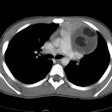

Posterior mediastinal masses:

Neurogenic tumors constitute between 20 to 40% of resected mediastinal neoplasms and the great majority are located in the posterior mediastinum. Neurogenic tumors are the most common cause of a posterior mediastinal mass [1]. Between 70-80% of the lesions are benign and approximately 50% of patients are asymptomatic. The vast majority of mediastinal neurogenic tumors are benign. Neurogenic tumors can be divided into 3 categories:1- Arising from peripheral nerves: Schwannoma, neurofibroma, and malignant tumors of nerve sheath origin

2- Arising from sympathetic ganglia: Ganglioneuroma, ganglioneuroblastoma, and neuroblastoma

3- Arising from paraganglia: Paraganglioma

- Lateral Thoracic Meningocele

- Other cause of posterior mediastinal masses include: Extramedullary hematopoiesis, Aortic aneurysm, Pancreatic pseudocyst, and Ectopic kidney